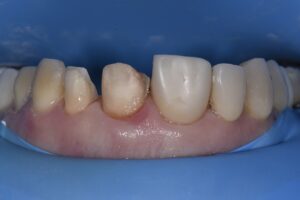

This nice 54 year old female desired a correction of her occlusal and gingival cant with simultaneous correction of the midline cant.  She rejected the option to complete gingivo-osseous recontouring at a separate appointment with a 2-3 month healing period as she had seen a previous case completed featuring osseous recontouring and preparations at the same time with good predictability.  The old Cerec leucite reinforced glass ceramic restorations were overcontoured and covering excessively prepared teeth along with exposed margins cervically.  A Digital Smile Design was completed for the patient indicating the extent of areas to be modified to gain near complete correction of the gingival and occlusal cant without being overly aggressive.

Following initial preparation from teeth 9-12 (2.1-2.4), the margins were located equigingivally.  From this point, the DSD was used as a guide to the change in cervical profile which was accomplished initially using the Ultradent Gemini diode Superpulsed laser at 1.2W in dual-wavelength mode.  The margins were relocated to this level, and a transsulcular approach using a Kois Wedelstaedt chisel was attempted and was generally successful except for a few problematic areas where re-establishment of ideal crestal distance from the margins was dubious.  A full thickness envelope flap was raised and the offending areas directly osteoplastied using the Kois Surgical System (Brasseler) prior to debriding the area and gaining primary closure using vertical mattress sutures.